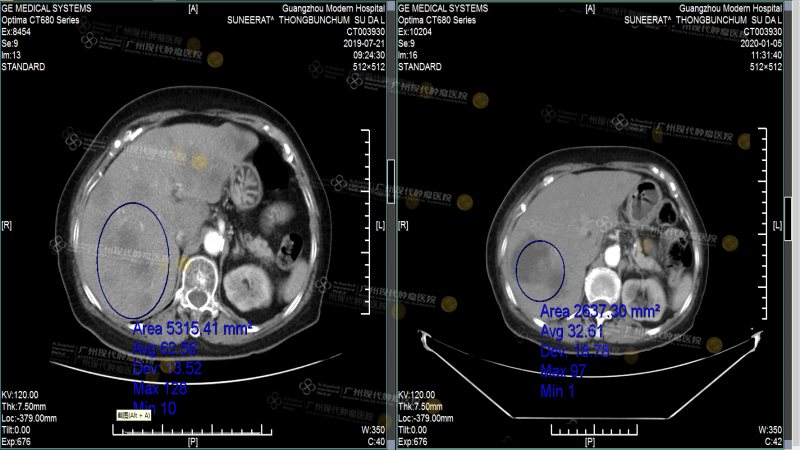

Vào tháng 7 năm 2019, trong quá trình kiểm tra định kỳ, tôi phát hiện bệnh tình bắt đầu xấu đi và đã tái phát, đồng thời xuất hiện di căn nhiều nơi, bao gồm cả gan. Con gái tôi ngay lập tức tìm kiếm các bệnh viện nổi tiếng và bác sĩ uy tín tại Thái Lan để tiếp tục điều trị, nhưng sau khi tìm đến nhiều nơi, các bác sĩ đều đưa ra một chẩn đoán giống nhau: tôi chỉ có thể sống thêm tối đa ba tháng nữa, từ đó cuộc sống của tôi buộc phải chuyển sang chế độ đếm ngược.

Sau khi nhập viện, bác sĩ đã thực hiện một loạt các xét nghiệm, tôi nhớ rất rõ quá trình kiểm tra, vì nó rất tỉ mỉ. So với các xét nghiệm tôi làm ở Thái Lan, bác sĩ ở đây hỏi rất kỹ và giải thích báo cáo kết quả rất rõ ràng. Sau khi có kết quả xét nghiệm, bác sĩ phát hiện các tế bào ung thư đã di căn sang gan, đồng thời xác nhận tôi bị ung thư vú tái phát sau phẫu thuật với di căn gan giai đoạn IV. Vì khối u quá lớn và số lượng quá nhiều, cùng với các bệnh nền như huyết áp cao cấp độ 3 và tiểu đường type 2, nhóm đa ngành MDT tại Bệnh viện Ung bướu St.Stamford Quảng Châu, dựa trên tiến triển bệnh lý và thể trạng của tôi, đã chọn phương pháp Vi sóng để tiêu diệt và giảm kích thước khối u gan. Phương pháp này sử dụng kim vi sóng để xuyên qua khối u vú và làm chúng hoại tử mà không cần phẫu thuật. Quá trình này rất ít đau đớn, phù hợp với tôi là một bệnh nhân cao tuổi. Sau khi khối u giảm kích thước, các bác sĩ tiếp tục kết hợp với điều trị can thiệp, dùng thuốc điều trị và thuyên tắc mạch cho khối u vú. So với hóa trị truyền thống, phương pháp này có nồng độ thuốc cao và không làm tổn thương các mô lành, rất phù hợp với thể trạng yếu ớt của tôi. Sau một loạt các liệu pháp điều trị này, các khối u của tôi đã giảm kích thước đáng kể và hoàn toàn đạt tiêu chuẩn sống cùng với khối u.